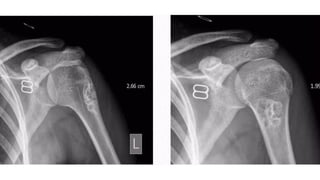

• An expansile lytic lesion

• S i z e = 2 - 2 0 c m

• Z o n e o f transition - can be ill-defined

• Thin sclerotic margin

• • Cortical breach and soft tissue extension

• CT & MRI

• • To delineate soft tissue extension

• • Shows characteristic fluid-fluid levels (representing areas of

• blood of variable ages)